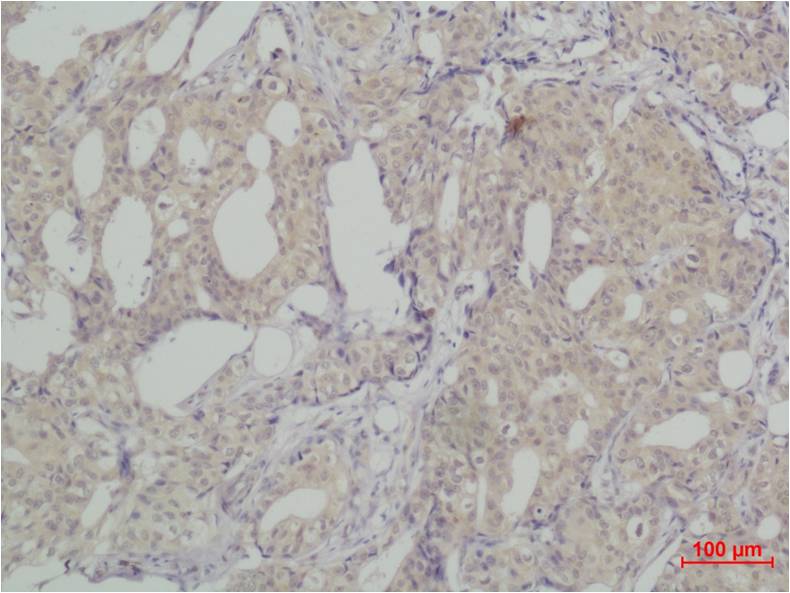

IHC 1/50-1/100 Human,Mouse,Rat

SNAI2 antibodies are widely used in research to detect and quantify SNAI2 expression in cells and tissues through techniques like Western blotting (WB), immunohistochemistry (IHC), and immunofluorescence (IF). These antibodies help elucidate SNAI2's regulatory mechanisms, interactions with signaling pathways (e.g., TGF-β, Wnt), and its role in maintaining cancer stem cell properties. Additionally, they aid in exploring SNAI2's involvement in developmental biology and fibrosis.